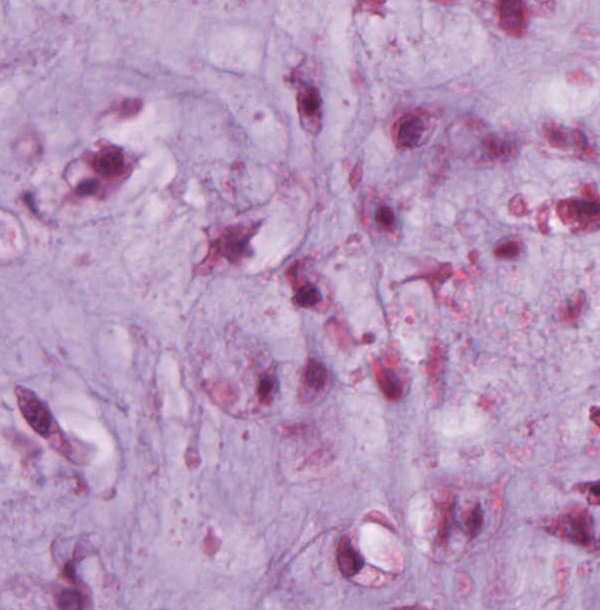

Mikroskopie

Die erkennbare chondroide Neoplasie ist knotig lobuliert aufgebaut, und enthält eine überwiegend basophil-hyaline, gering bis mäßig myxoid aufgelockerter Grundsubstanz mit unterschiedlicher Zelldichte. Die Zellen bestehen aus ein-, gelegentlich binukleär gestalteten chondroiden fokal deutlich eosinophilen Zellelementen. Weiterhin zeigt sich eine ausgeprägte Nekrotisierung und eine Infiltration von knöchernen und angrenzenden Weichgewebe. Die Tumorformationen reichen bis in den knöchernen Präparaterand.